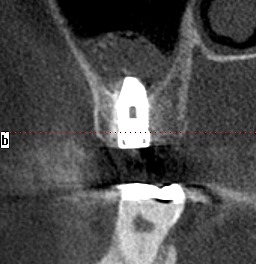

埋入後のCTになります。| |広島市安佐南区の歯科医院 埋入後のCTになります。 トップ お知らせ・ブログ 埋入後のCTになります。 埋入後のCTになります。 Web診療予約 初めての方へ 選ばれ続ける理由 院内設備について 歯が痛いしみる一般歯科 歯がぐらぐらする歯周病 健康な歯を保ちたい予防歯科 子供の虫歯予防をしたい小児歯科 銀歯をセラミックに審美歯科 白い歯を目指しませんか?ホワイトニング 矯正専門医がいるので安心矯正歯科 抜けた歯を補いたいインプラント・入れ歯 医院案内 スタッフ紹介 メリィハウス歯科クリニックオフィシャルホームページ ラベンダー歯科クリニックオフィシャルホームページ お知らせ・ブログ ホーム 診療科目 一般歯科 歯周病治療 予防治療 小児歯科 審美治療 ホワイトニング 矯正歯科 入れ歯・インプラント マウスピース矯正 初めての方へ 院長・スタッフ 設備紹介 医院案内・アクセス メニューを閉じる